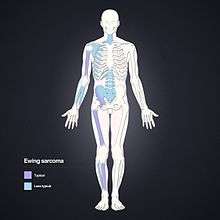

Ewing's sarcoma or Ewing sarcoma (/ˈjuːɪŋ/) is a malignant small, round, blue cell tumor. It is a rare disease in which cancer cells are found in the bone or in soft tissue. The most common areas in which it occurs are the pelvis, the femur, the humerus, the ribs and clavicle (collar bone).

Ewing's sarcoma is more common in males (1.6 male:1 female) and usually presents in childhood or early adulthood, with a peak between 10 and 20 years of age. It can occur anywhere in the body, but most commonly in the pelvis and proximal long tubular bones, especially around the growth plates. The diaphyses of the femur are the most common sites, followed by the tibia and the humerus. Thirty percent are overtly metastatic at presentation. Patients usually experience extreme bone pain.

Staging attempts to distinguish patients with localized from those with metastatic disease.[29] Most commonly, metastases occur in the chest, bone and/or bone marrow. Less common sites include the central nervous system and lymph nodes.